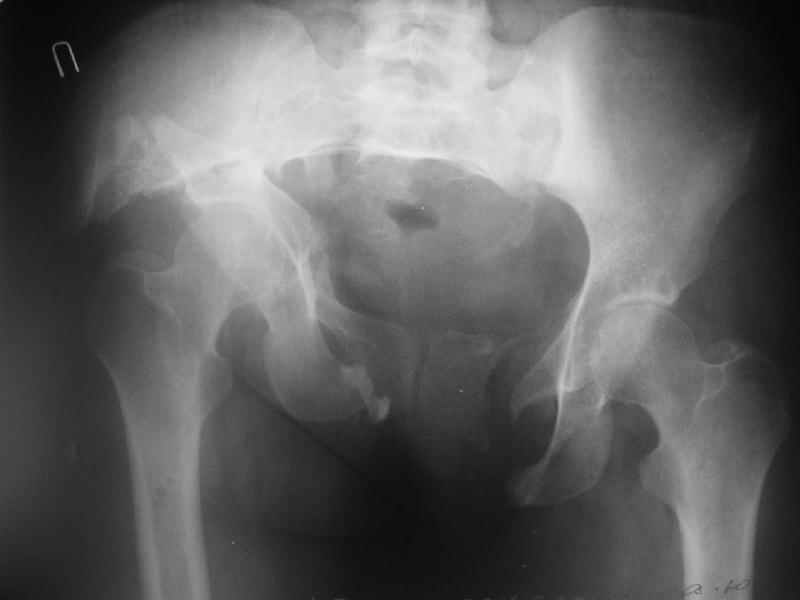

Картина на сегодня:

В настоящее время больная ходит без дополнительной опоры, боль в области таза не беспокоит, неудобств при сидении не испытывает, свободно проходит расстояние в 2-3км. Отмечается незначительная хромота, периодические боли в поясничной области низкой интенсивности, не требующие приема медикаментов, кроме того имеется вагинальный импинджемент. Срок после операции 1 год и 2 месяца.Было бы интересно услышать ваши комментарии. С уважением Агалаков М.В.